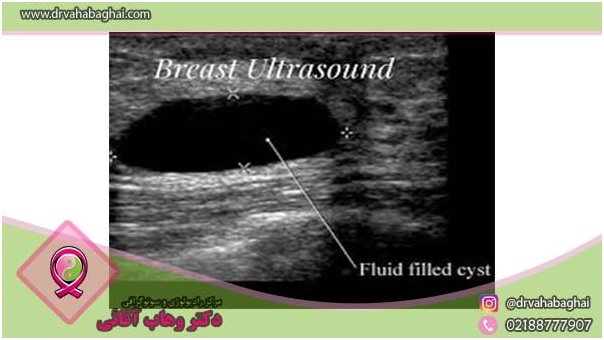

سونوگرافی

گاهی اوقات از سونوگرافی در کنار آزمایش ماموگرافی استفاده می‌شود. سونوگرافی در تشخیص ناهنجاری‌ها در زنان جوان‌تر از سی سال که بافت پستان متراکم‌تری دارند از ماموگرافی مؤثرتر عمل می‌کند. در سونوگرافی، تفاوت بین کیست‌ها و توده‌های متراکم پستان بهتر تشخیص داده می‌شود.